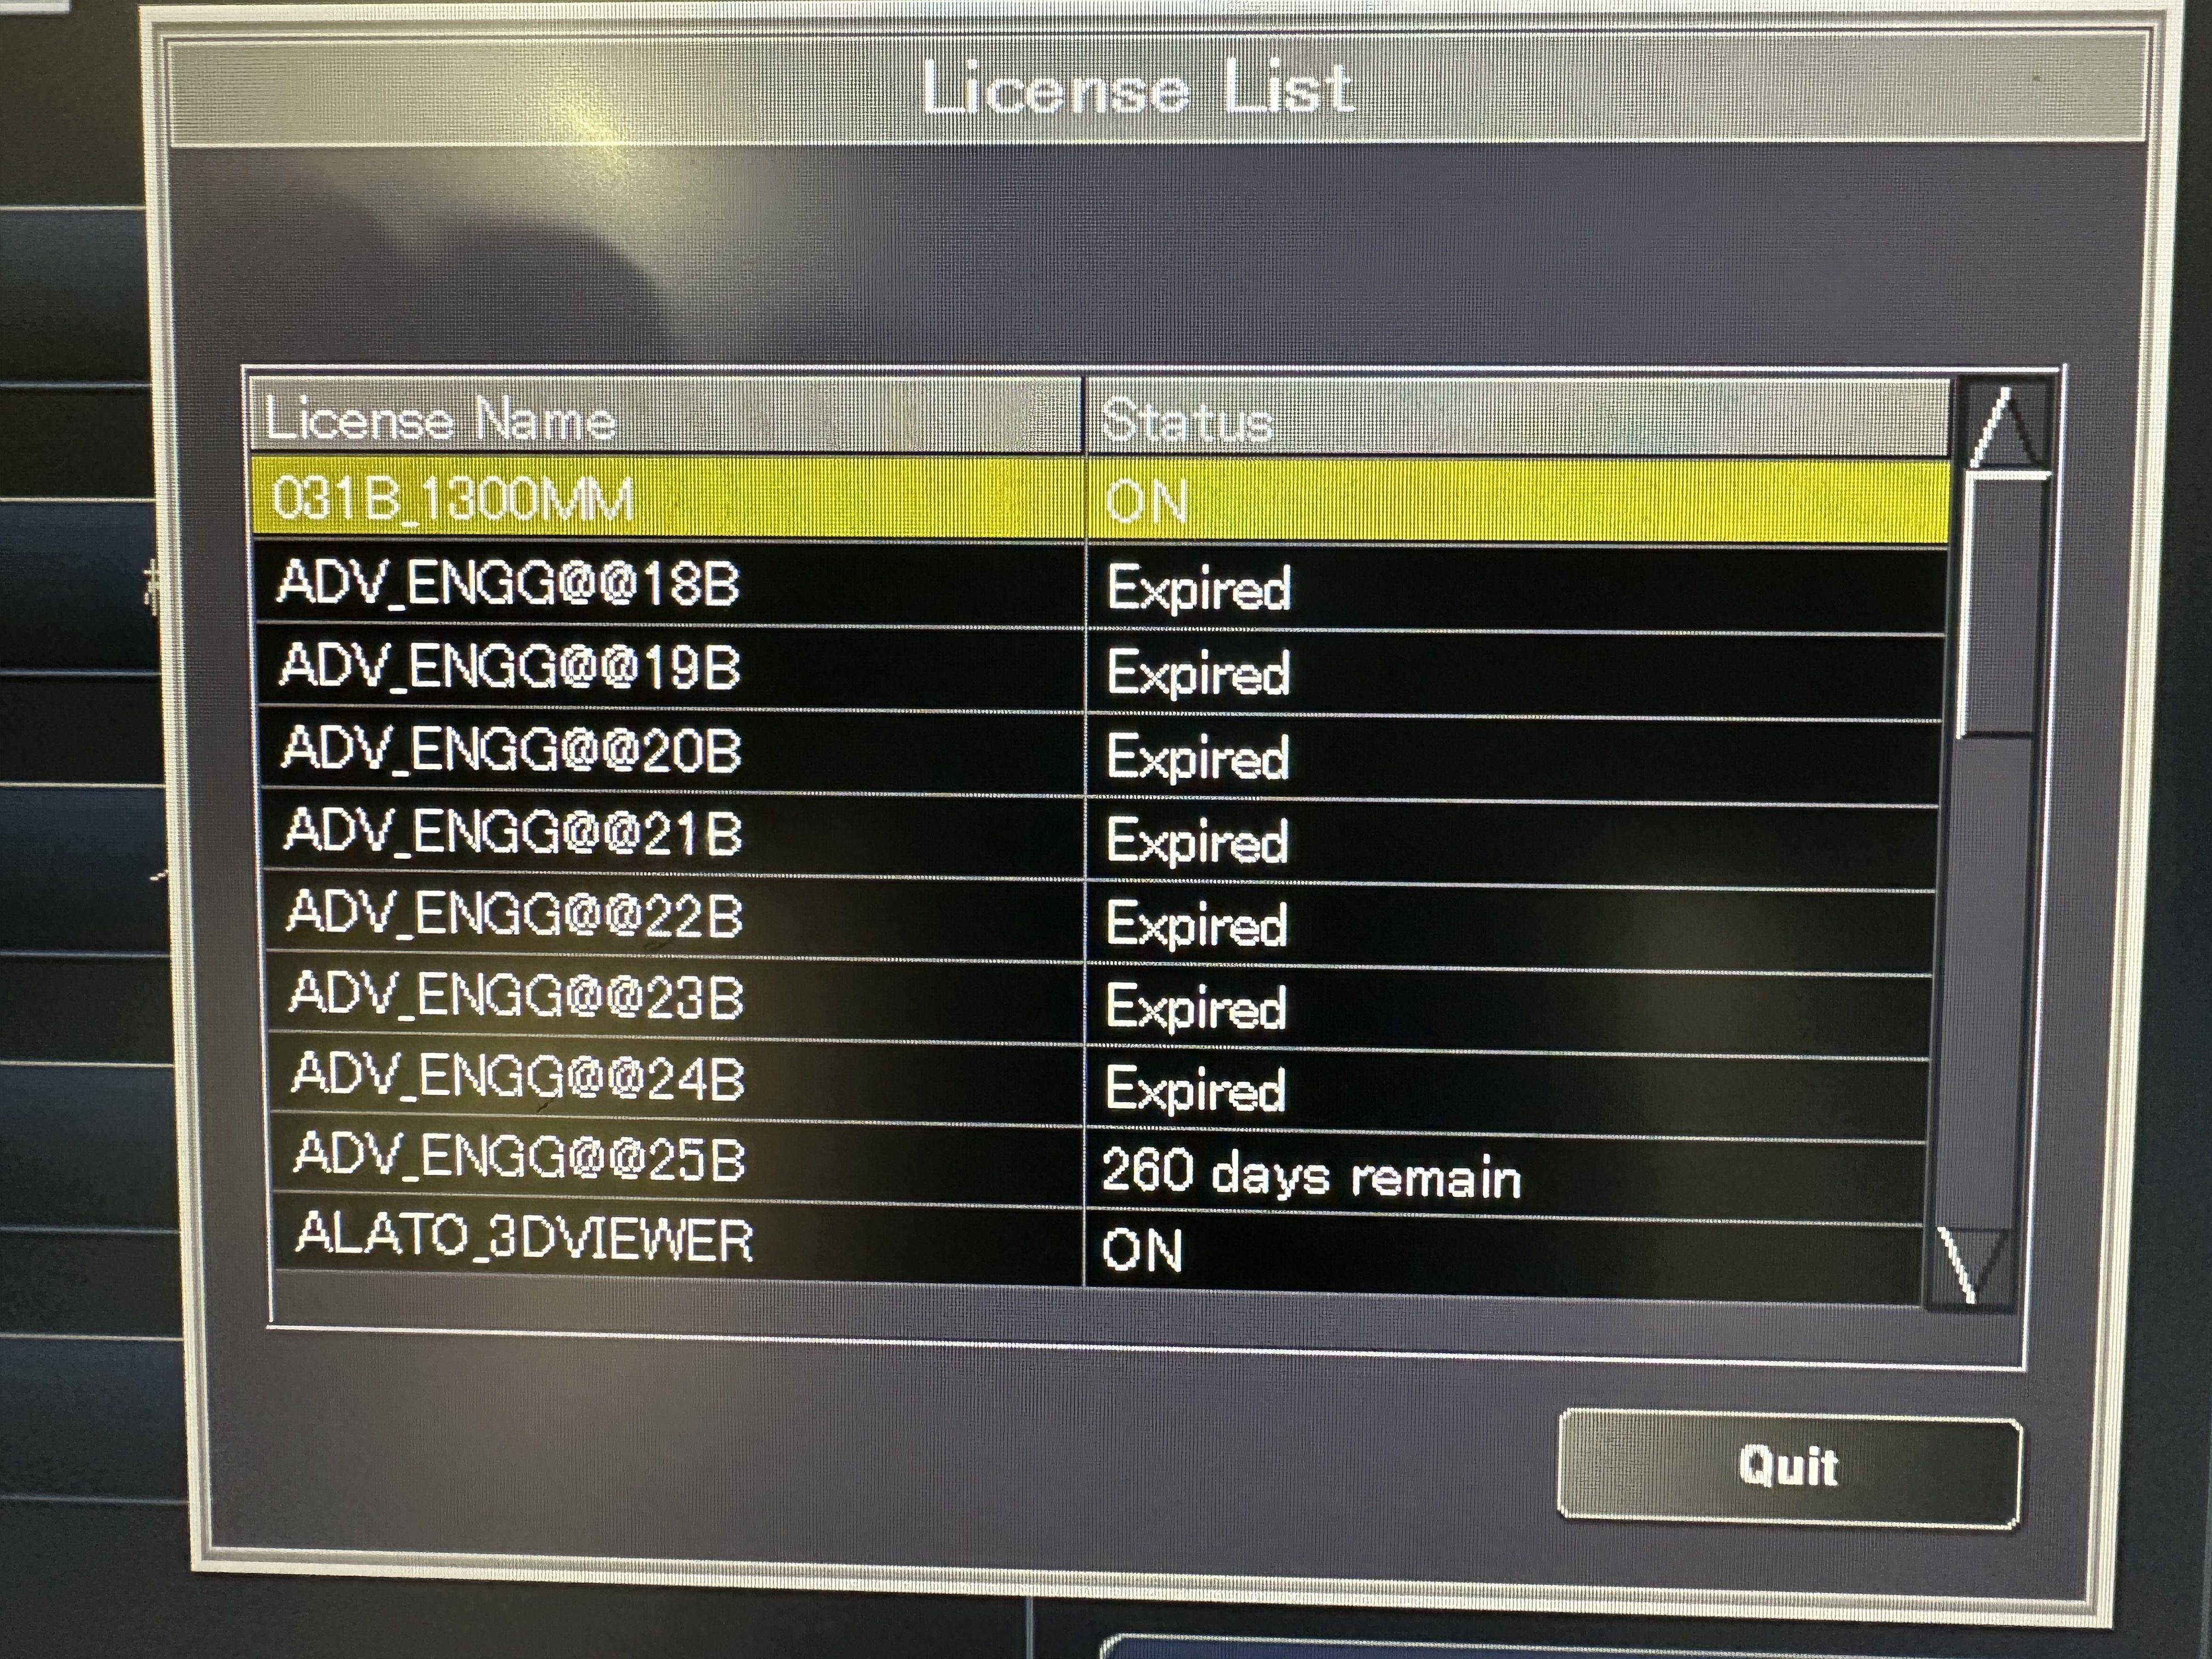

| Installed Options | : | ALATO_3DVIEWER, ALATO_MULTISLICECT, ALATO_STANDARD, DCM_CDR, DIM_EXP, DOUBLESLICE, D_PRT_BW, D_PRT_COLOR, MULTIVIEW, PRINT_SCU, REALEC, REAL_PREP, REAL_VIEW, STRG_SCU, TIFF, TOS_SERVICE, TSB_DVD, WINPRT |